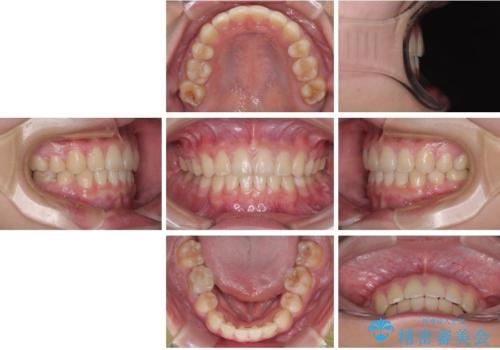

そのため、限られた期間内に効率よく治療を完了するために、「抜歯スペースの確実な閉鎖」「深い噛み合わせ(過蓋咬合)の改善」の2点を主軸とした治療計画を立てました。

結果的に1年半で、再度転勤になる前に治療を終えることができました。